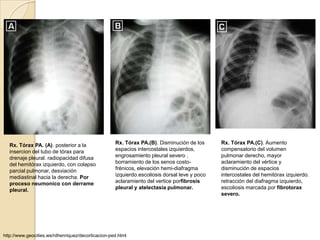

Rx. Tórax PA. (A). posterior a la                 Rx. Tórax PA.(B). Disminución de los      Rx. Tórax PA.(C). Aumento

insercion del tubo de tórax para                  espacios intercostales izquierdos,        compensatorio del volumen

drenaje pleural. radiopacidad difusa              engrosamiento pleural severo ,            pulmonar derecho, mayor

del hemitórax izquierdo, con colapso              borramiento de los senos costo-           aclaramiento del vértice y

parcial pulmonar, desviación                      frénicos, elevación hemi-diafragma        disminución de espacios

mediastinal hacia la derecha. Por                 izquierdo.escoliosis dorsal leve y poco   intercostales del hemitórax izquierdo.

proceso neumonico con derrame                     aclaramiento del vertice porfibrosis      retracción del diafragma izquierdo,

pleural.                                          pleural y atelectasia pulmonar.           escoliosis marcada por fibrotorax

severo.